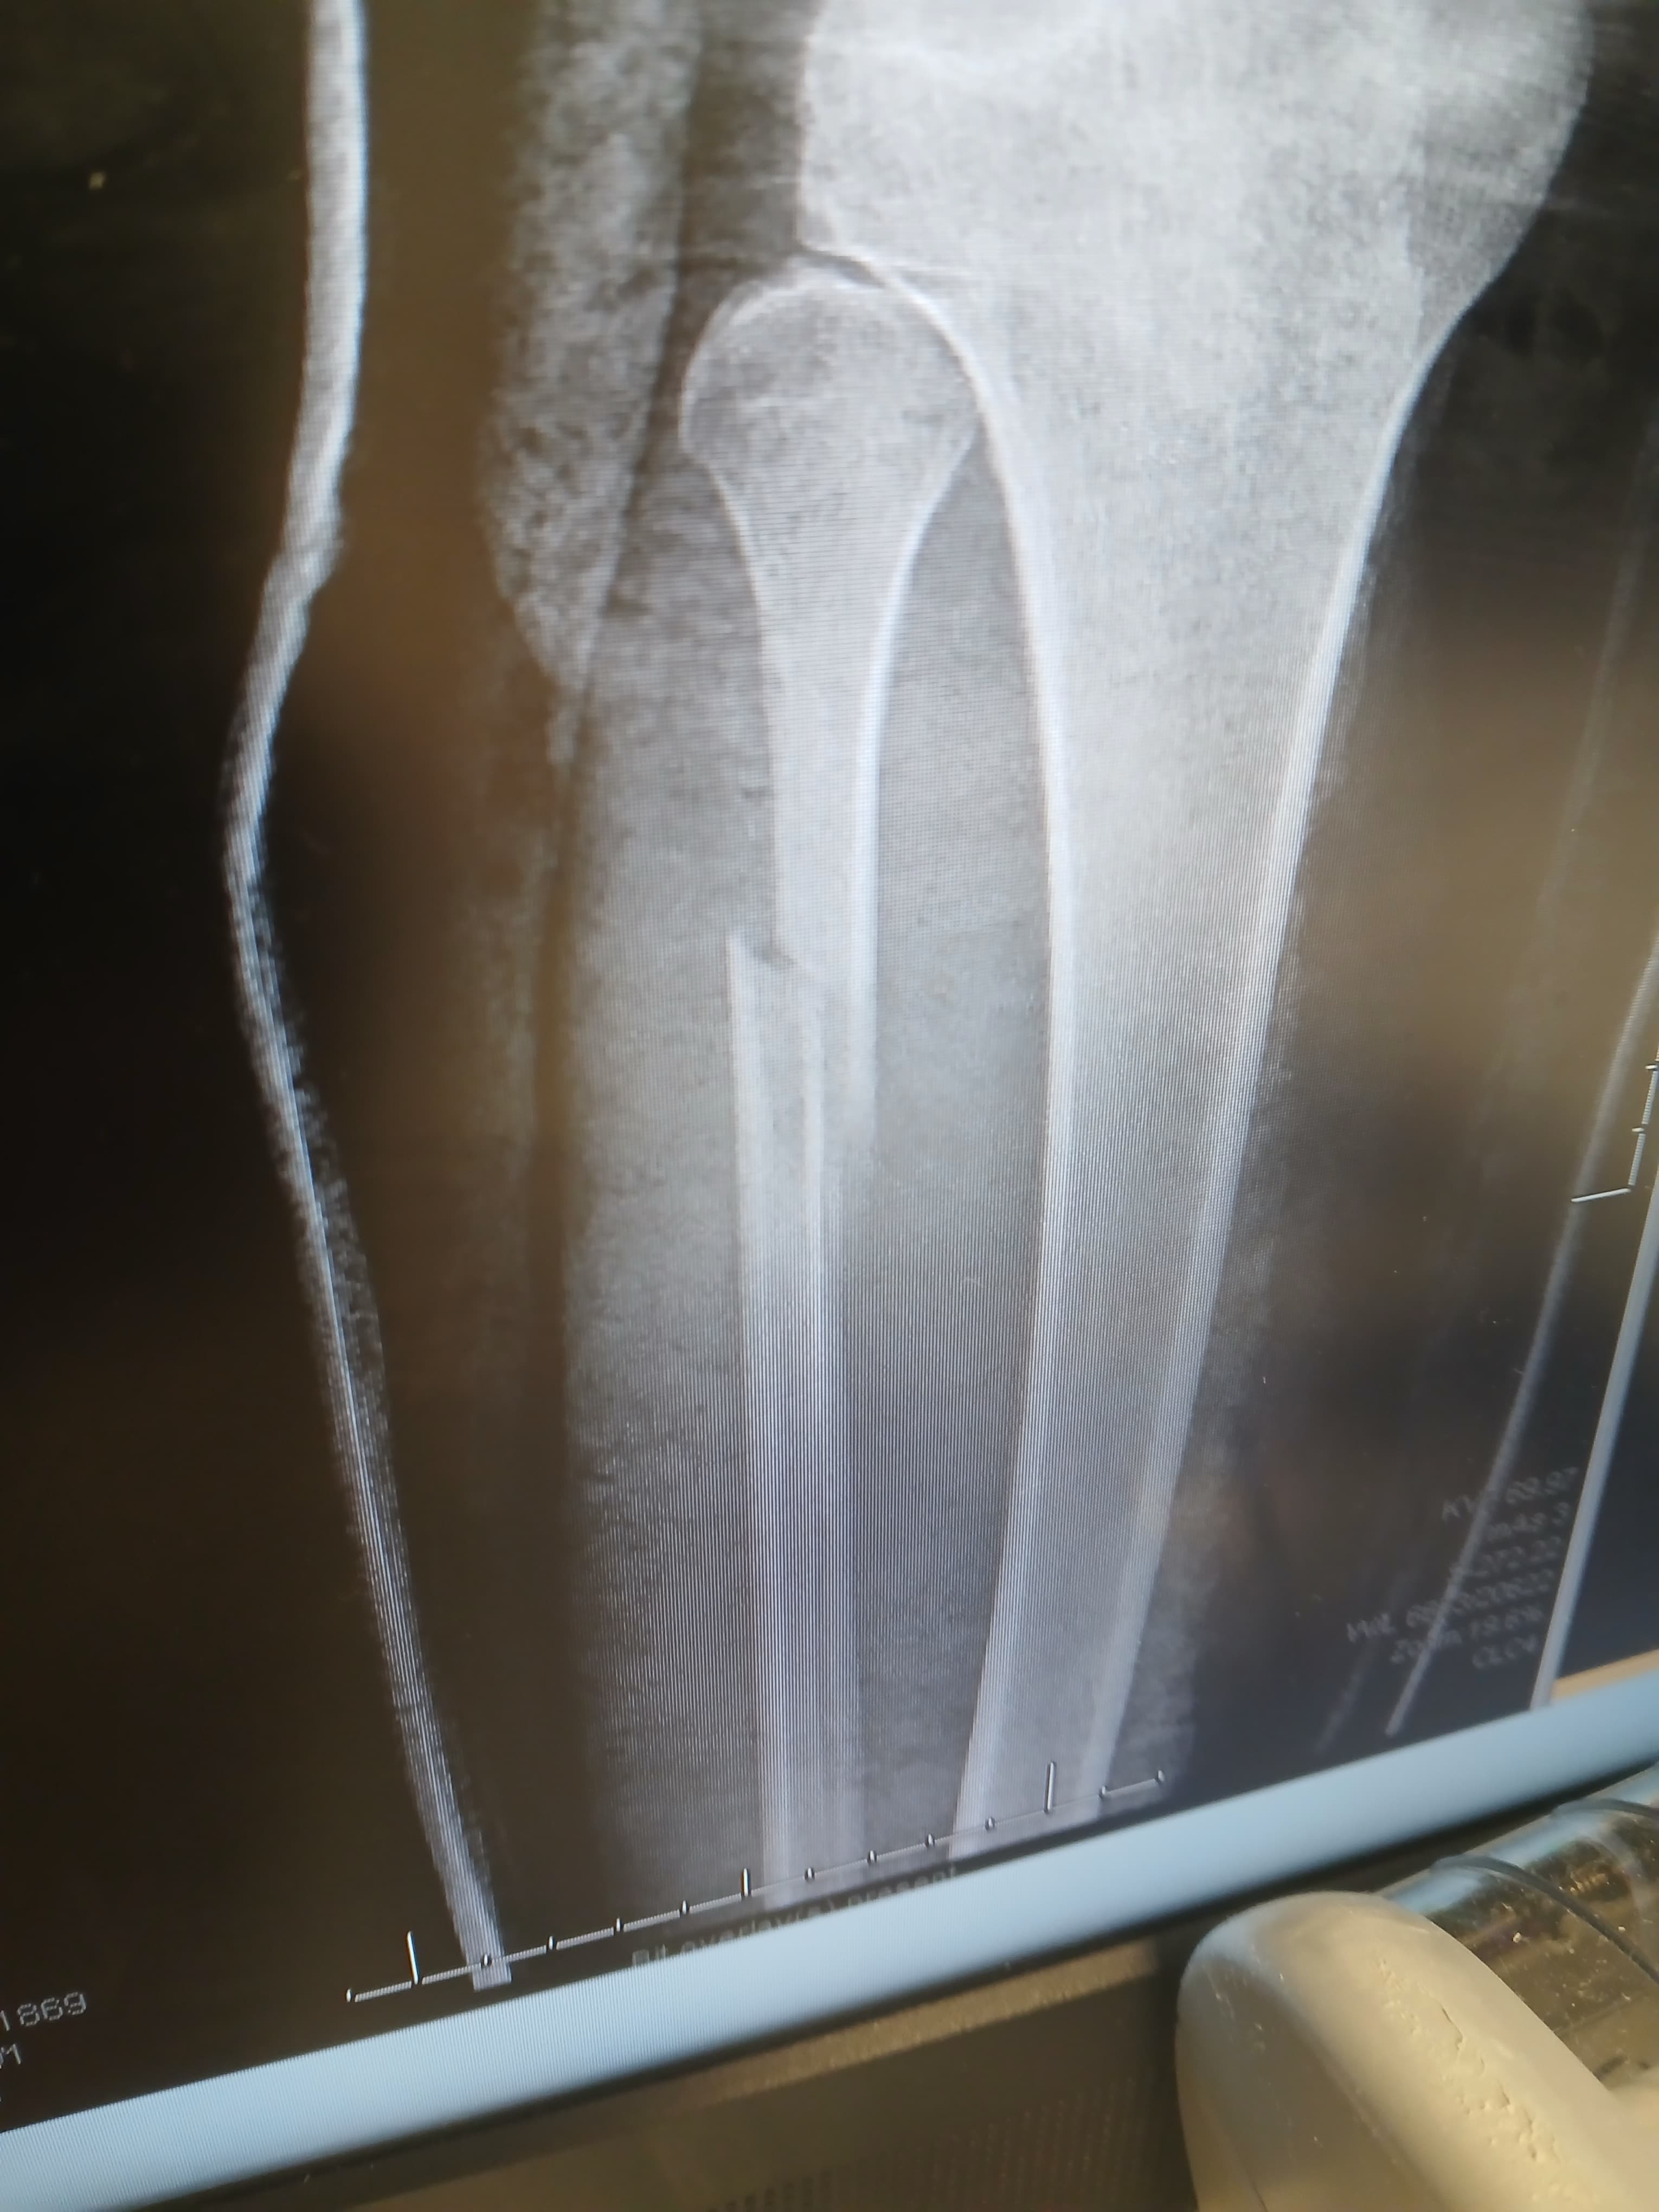

My name is Cristal, and I recently slipped on ice during a bad storm, breaking my leg in two places. The accident happened so quickly, and it has completely changed my daily life. I am now facing a long recovery, unable to work, and struggling to manage even simple tasks on my own. The pain and stress have been overwhelming, and I am worried about how I will keep up with my 2 children, medical bills and rent while I heal.